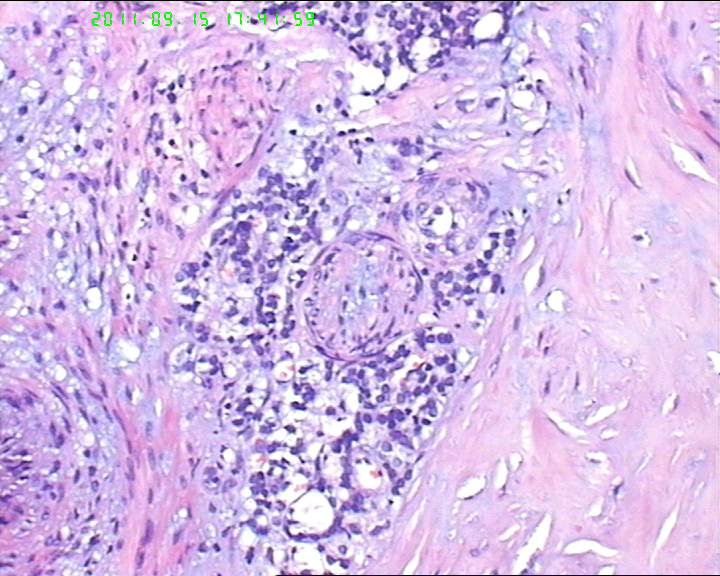

38岁女性甲状腺,腺瘤?滤泡癌?

甲状腺右下极一肿物,3*3大小,切面灰红实性质韧,可见部分包膜,一侧可见一空腔,未见内容物。

38岁女性甲状腺,腺瘤?滤泡癌?图3

名称:图3

描述:20110915-3.jpg.jpg

够不够滤泡癌,要找有没有浸润。网友们,这么多图片,有包膜浸润吗(哪几张是包膜)?图12、14又是什么?

同意李老师的观点。该例目前为止无一张图片显示总体包膜情况(有无包膜,是否腺瘤)。建议楼主上传低倍镜图片。